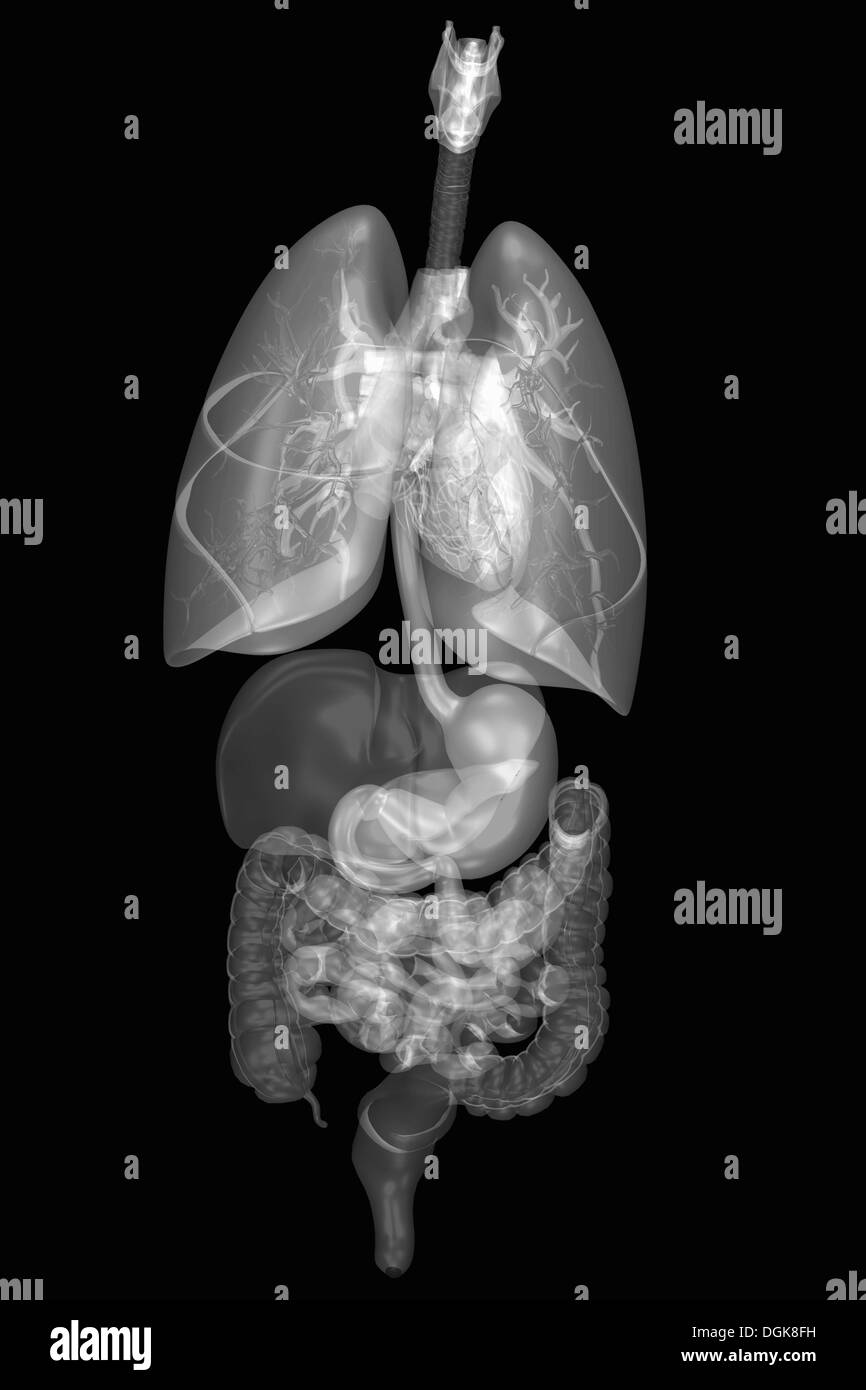

Internal human anatomy and organ systems Stock Photohttps://www.alamy.com/image-license-details/?v=1https://www.alamy.com/internal-human-anatomy-and-organ-systems-image61889397.html

Internal human anatomy and organ systems Stock Photohttps://www.alamy.com/image-license-details/?v=1https://www.alamy.com/internal-human-anatomy-and-organ-systems-image61889397.htmlRFDGK8FH–Internal human anatomy and organ systems